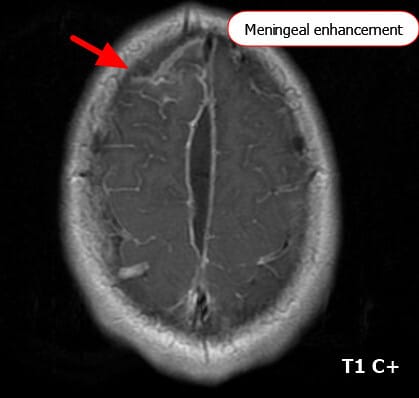

주요 MRI 소견

세균성 수막염에서는 조기 진단과 합병증 파악을 위해 MRI를 시행합니다.

🔵 수막 조영 증강(Meningeal Enhancement)

가장 흔한 소견입니다. 특히 조영증강 MRI(T1 + gadolinium)에서 뇌 표면을 따라 선명한 조영증강이 보입니다.

주로 지주막하 공간(subarachnoid space)을 따라 나타나며, 균이 염증을 일으켜 혈관 투과성이 증가하기 때문입니다.